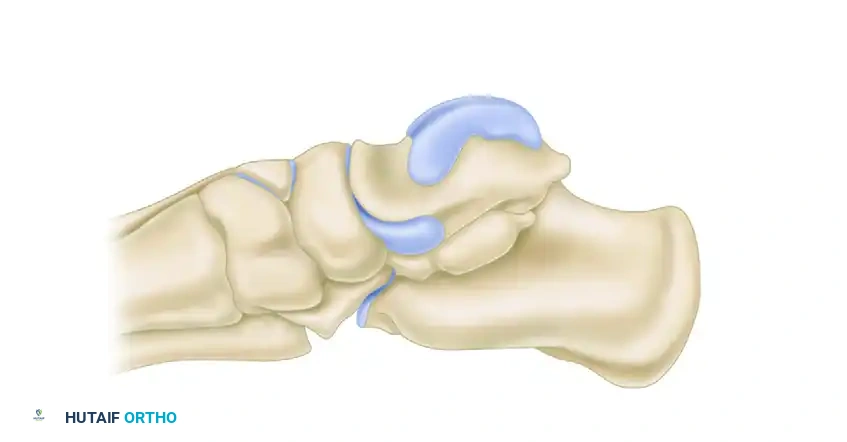

Angles of middle and posterior subtalar facets demonstrating the high variability in normal hindfoot anatomy.

Diagrammatic representation of the posterior facet orientation.

Further diagrammatic representation of the posterior facet.